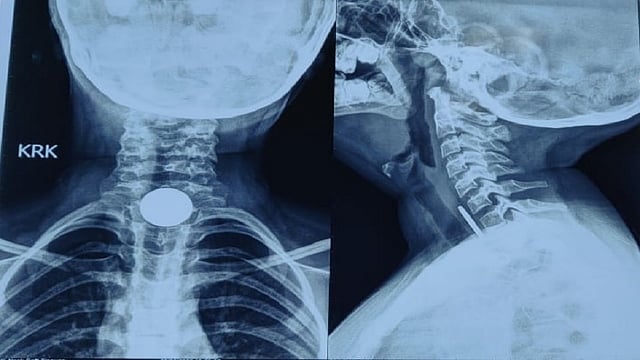

लाॅकडाऊनमध्ये लहान मुलांना कोरोनाचा संसर्ग होऊ नये म्हणून याची काळजी घेण्यात आई-वडील व्यस्त असताना आता त्यांना लहान मुलांकडे विशेष लक्ष द्यायची गरज आहे. अंधेरीतील मुलाने घरी असताना अचानकपणे नाणे गिळले. ते त्याच्या अन्ननलिकेच्या वरील भागात अडकले. या ब्लॉकेजमुळे त्याला प्रचंड वेदना होऊ लागल्या आणि काहीही खाऊ लागल्यास त्याला उलटी होत होती. पालकांनी स्थानिक नर्सिंग होममध्ये काढलेल्या एक्स-रेमध्ये नाणे दिसून आले. अनेक डॉक्टरांना भेटल्यानंतर ते नानावटी रुग्णालयात दाखल झालेत.

मुलगा हाॅस्पिटलमध्ये दाखल झाल्यानंतर सिनियर कन्सल्टंट आणि ईएनटी स्पेशलिलस्ट डॉ. अमोल पाटील यांनी मुलाची तपासणी केली. नाण्यामुळे मुलगा खूप अस्वस्थ होता. दरम्यान घशातील नाणं काढण्यात आणखी उशीर झाला असता तर अन्न नलिकेत संसर्ग होऊन मुलाला धोका होऊ शकतो या भीतीने त्यांनी इन्डोस्कोपिक प्रक्रिया करण्याचा निर्णय घेतला. आवश्यक सर्व खबरदारी घेत डॉक्टर पाटील यांच्या सर्जिकल टीमने एसोफॅगोस्कॉपी- एंडोस्कोपिक प्रक्रिया केली. यामध्ये धातूच्या रॉडमध्ये सुरक्षितपणे लपवून ठेवल्या फोर्सेप्सच्या मदतीने डॉक्टरांच्या पथकाने काही वेळातच नाणे यशस्वीरित्या बाहेर काढले.